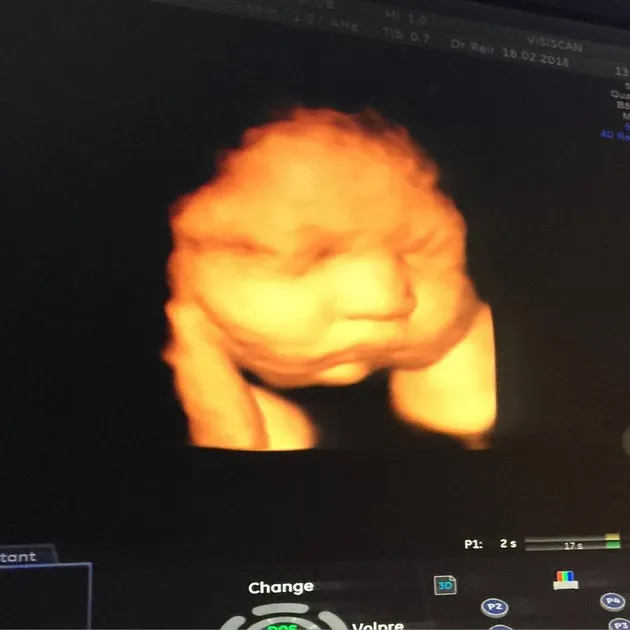

Tantri pun sempat menjalani USG, dan mendapatkan banyak foto dari buah hatinya bahkan sebelum lahir.

Hak Cipta: instagram.com/tantrisyalindri